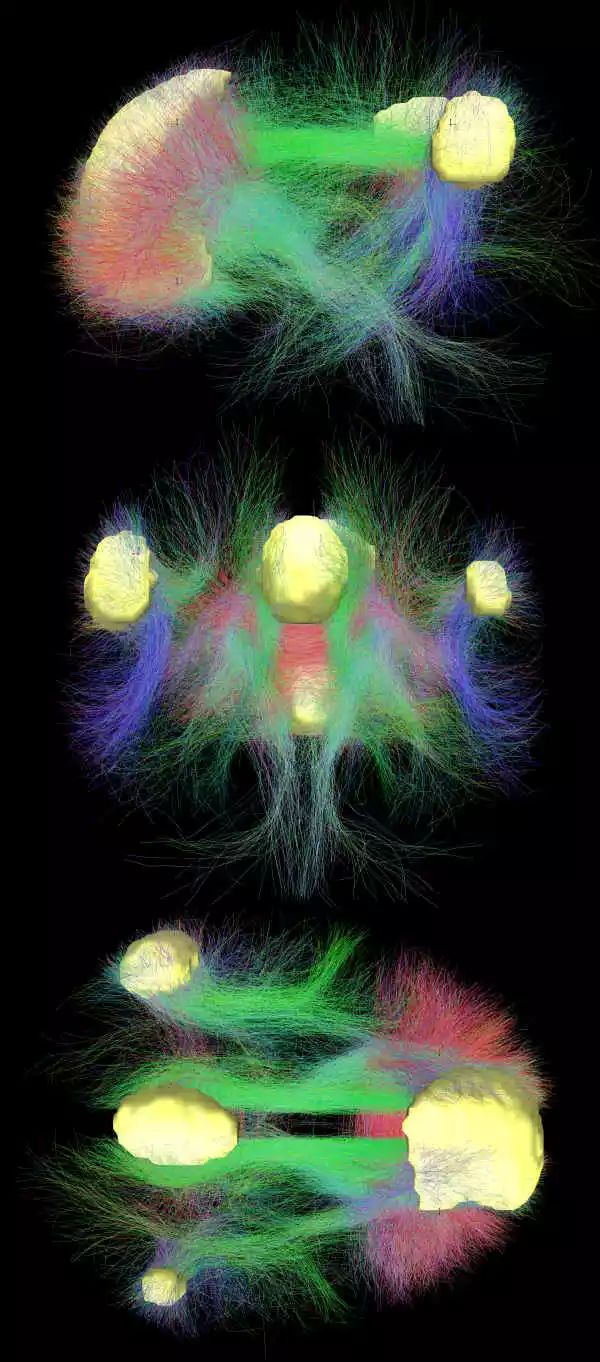

作者得出结论,“人类的心灵是走神的心灵,走神的心灵是不高兴的心灵。”任何静修(silent retreat)过的人都同意这一点。 (www.ncbi.nlm.nih.gov/pmc/articles/PMC1821121/) 走神的心灵与大脑中线区域的活动有关,特别是内侧前额叶皮层和内侧顶叶皮层。

这些区域通常被叫做“默认模式”或“静息模式”回路,因为我们在无所事事、等待事件发生的时候这些区域最活跃。

在大多数神经影像实验中,每当被试开始集中注意力到某种任务上时,默认模式网络(default-mode network ,DMN)的活跃程度就开始下降。 1529382014024e774368427 功能性磁共振显示下的默认模式网络。图源:wikipedia DMN还与我们进行“自我表征”的能力有关。例如,如果某人相信自己个子高,那么“高”这个词在DMN区域激起的信号就比“矮”这个词更强烈。

类似的,当我们对自己做判断,而非对别人做同样判断时,DMN区域也更活跃。

还有,当我们用第一人称视角而非第三人称视角来评估某场景时,DMN区域更加活跃。

大体上来讲,向外集中注意力会减弱大脑中线区域的活动,而思索自身则会增强该区域的活动。这些结果相互印证,可能解释了我们“忘我投入工作”的共同体验。

正念冥想(mindfulness meditation)和慈心禅(loving-kindness meditation)也能减弱DMN区域的活动,这种效应在经验丰富的冥想者身上体现得尤为明显,而且无论是冥想还是休息时都有效果。

尽管从这些发现得出强结论还为时尚早,但它们的确暗示了“走神体验”和“自我感知”可能有某种脑回路上的关联,毕竟冥想能通过某种可能的共同机制来削弱两者。 1529382014452a54a6587b0 该图显示了默认模式神经网络(黄色区域)之间按照颜色编码的区域连通性。图源:wikipedia